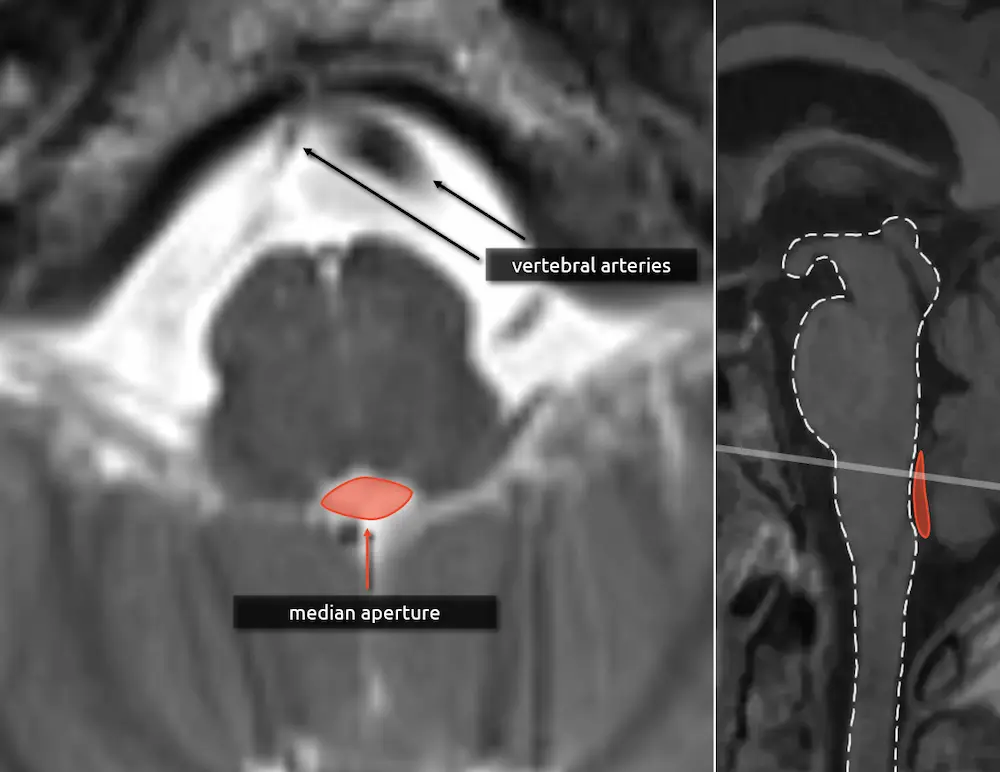

The lateral borders of the medulla are concave compared to the bulbous, convex borders of the pons.

1. Median aperture

The median aperture, or the foramen of Magendie, is the thin CSF space posterior to the medulla and medial drainage pathway of the fourth ventricle. There are two more holes in the lateral aspect of the fourth ventricle, called the lateral apertures or foramina of Luschka. Together, these are the three ways that CSF can flow inferiorly into the cisterna magna.

2. Vertebral arteries

The vertebral arteries fuse to form the basilar artery approximately at the level of the upper medulla. If they are present, then you are likely at the level of the medulla in the absence of variant anatomy (e.g. basilar nonfusion).